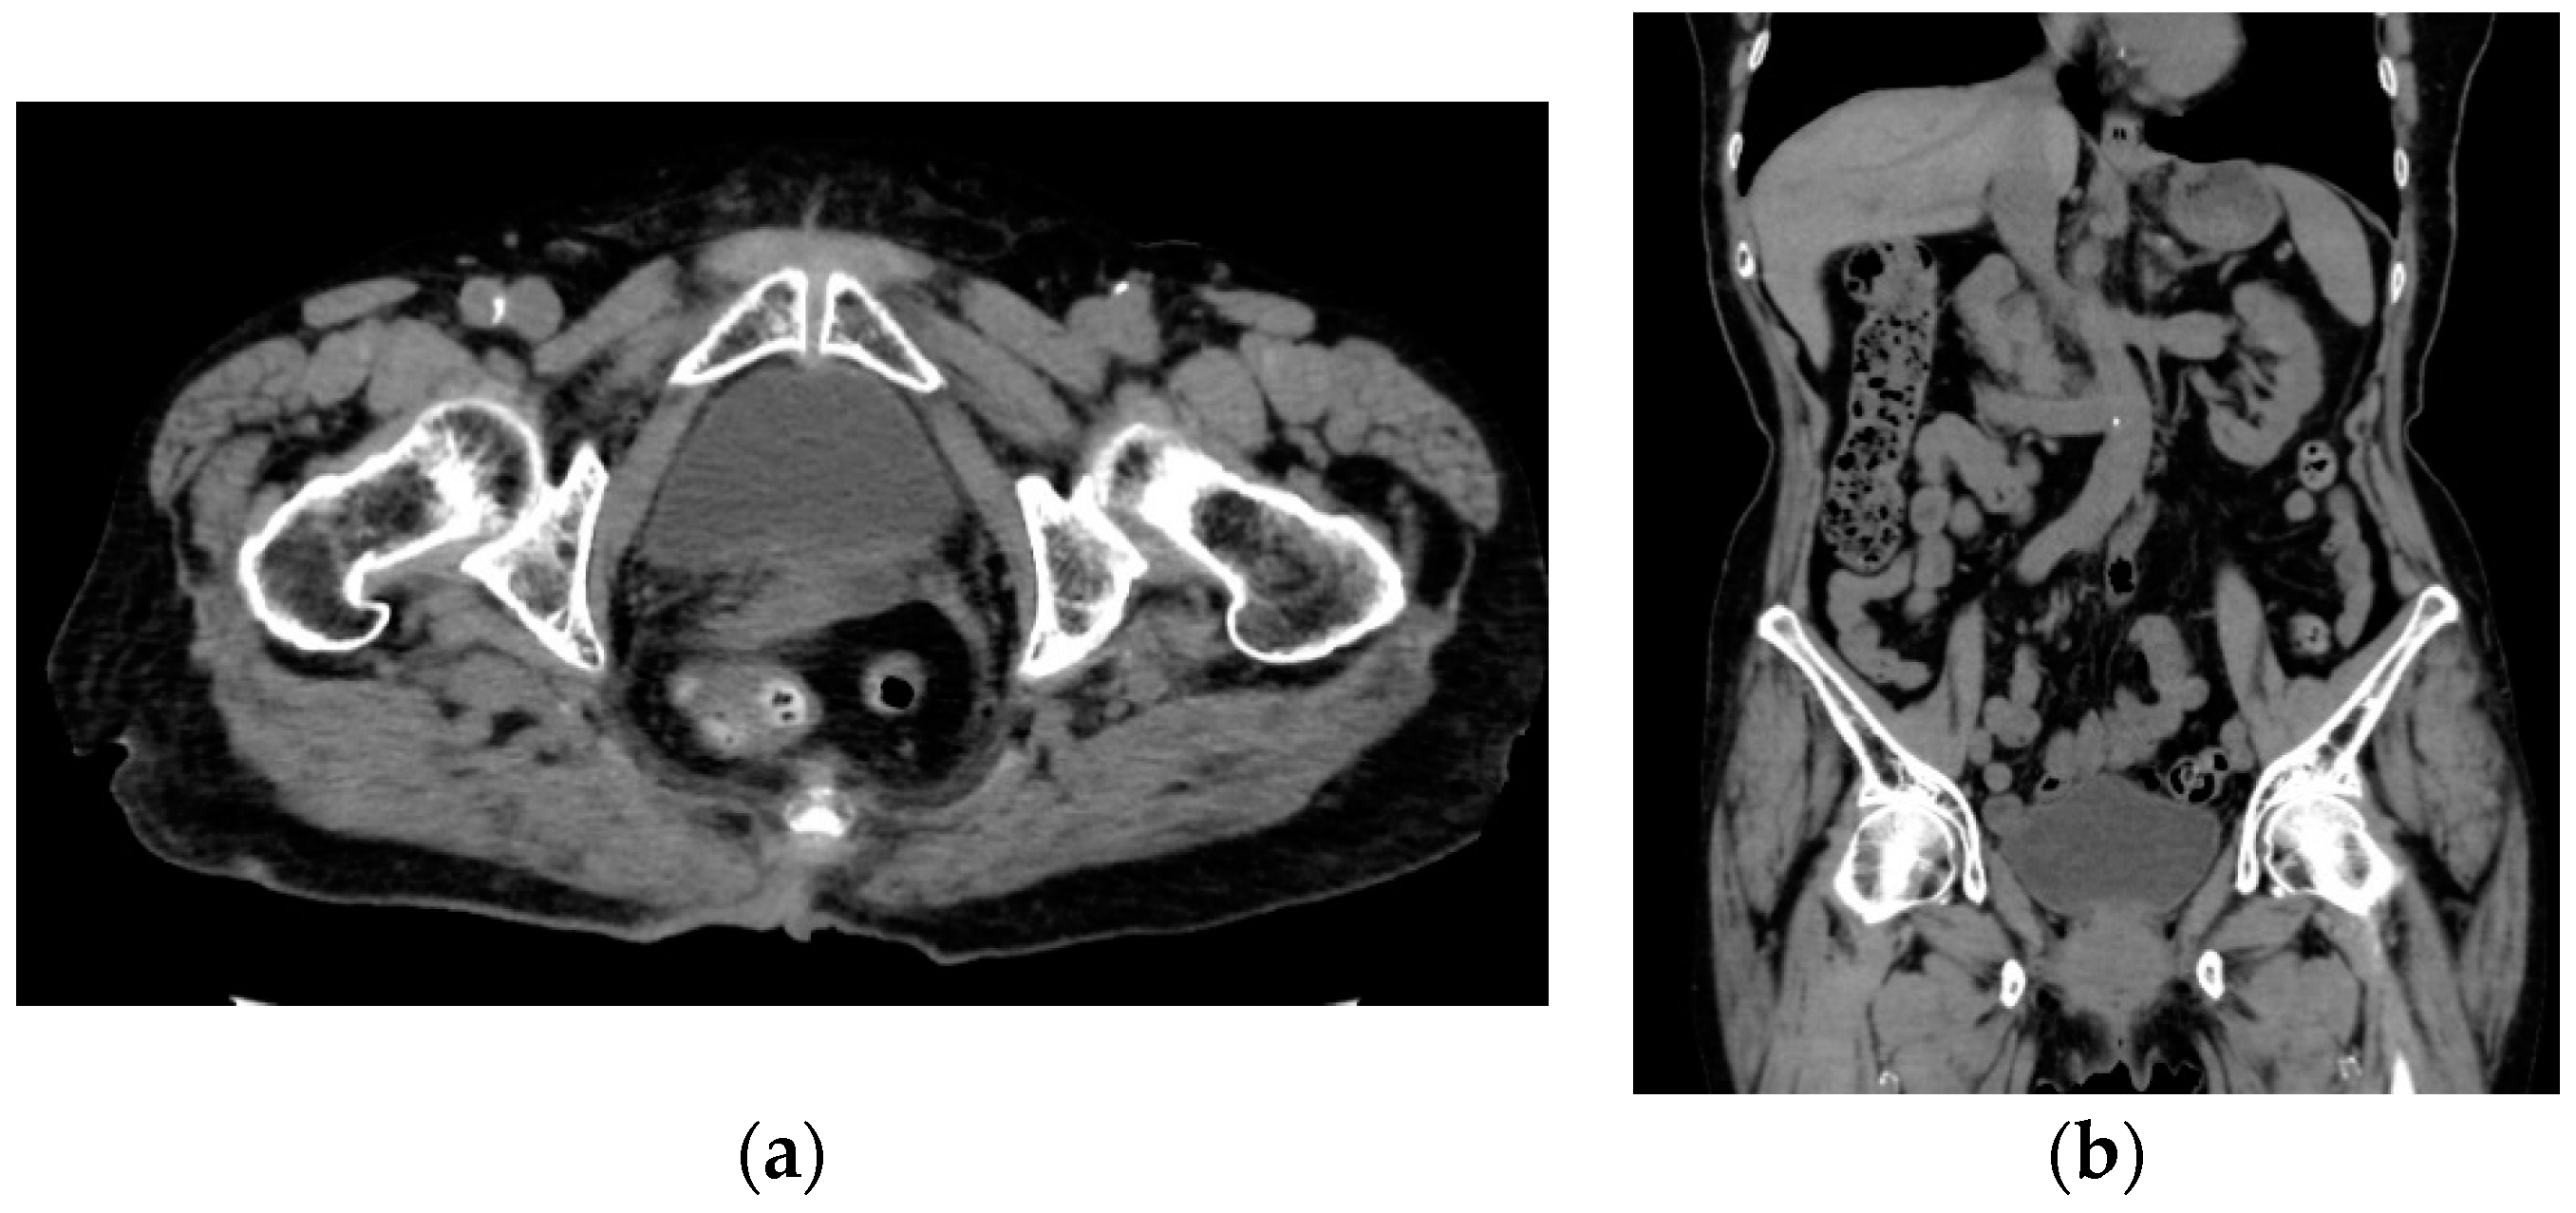

2. Case Presentation